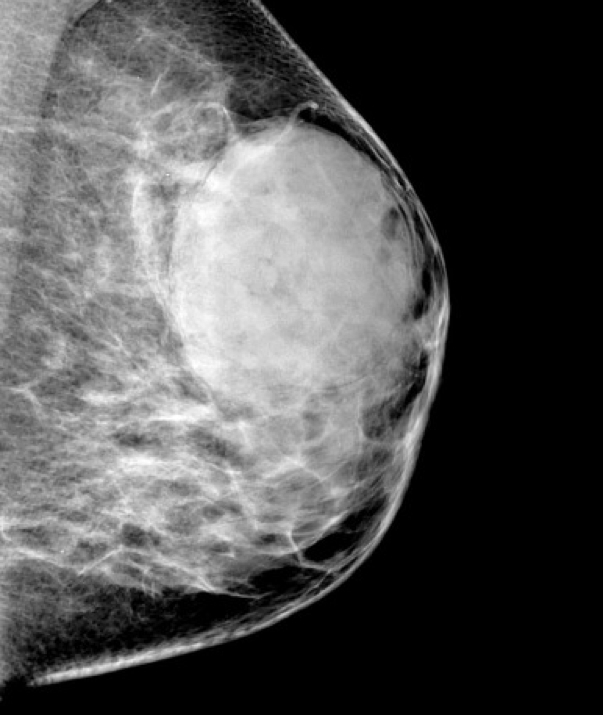

Phyllodes Tumour (Giant Fibroadenoma)

- Similar origin to fibroadenoma: benign tumour of intralobular stroma with glandular elements

- Common in older women (50–60 years)

- Capsulated, firm, grey nodular mass

- Distinguished by “phyllodes” (leaf-like) clefts and slits

- Typically benign but locally aggressive

- May recur without excision

- Can be premalignant, especially in older patients

- Expanding lesion without nipple retraction

- Metastasis is rare

- Surgical excision recommended to prevent recurrence

2. Credit: https://radiopaedia.org/articles/giant-fibroadenoma